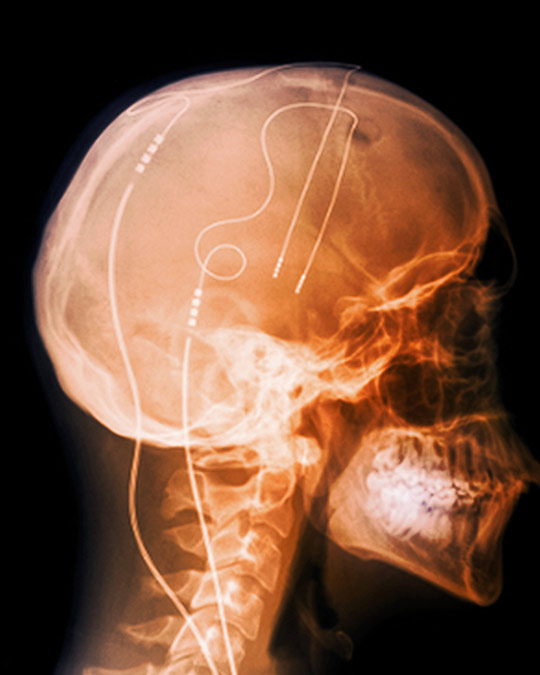

Dyp hjernestimulering i basalgangliene kan gi god symptomkontroll ved alvorlig Tourettes syndrom.

Illustrasjonsfoto: Science Photo Library

Dyp hjernestimulering er en etablert behandling av flere bevegelsesforstyrrelser som Parkinsons sykdom, tremortilstander og dystoni (1).

I en studie publisert i Lancet Neurology ble det satt inn bilaterale elektroder i globus pallidus internus hos 15 pasienter med alvorlig Tourettes syndrom (2). Pasientgruppen ble så randomisert i to grupper, der halvdelen hadde pulsgeneratoren slått i tre måneder fulgt av tre måneder der den var slått av, mens de resterende hadde generatoren først slått av i tre måneder fulgt av tre måneder der den var slått . Hjernestimulering ga signifikant reduksjon i både motoriske og vokale tics. I perioden etter at den randomiserte delen av studien var avsluttet, var symptomene enda mindre uttalte, fordi man fikk anledning til å finjustere hjernestimuleringen.